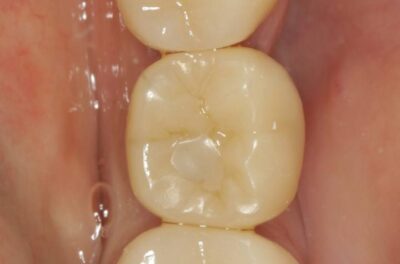

Протезирование коронками из диоксида циркония, после эндодонтического лечения — Исламов Л.А.(01.04.2026)